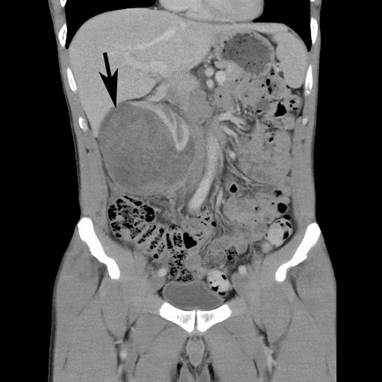

A 43-year-old Caucasian man, with a 4-week history of right upper quadrant and right flank pain radiating to his right testicle, presented to his general practitioner. There was no preceding trauma, haematuria or any other systemic symptoms. The past medical history included osteoid osteoma in the left upper femur, which was removed in 2007. He also had L4/5 microdiscectomy. There was no positive family history of medical problems or cancer. He was a non-smoker, had no allergies and was not taking any regular medications. The general practitioner organized an ultrasound, which revealed a large subcapsular haematoma measuring 7 × 5 × 7 cm in the right kidney compressing the renal cortex. Further investigation with computed tomography (CT) scan of the abdomen with intravenous contrast revealed enlarged right kidney with subcapsular haematoma and a mass lesion within the right lower pole measuring up to 7.4 × 7.5 × 9.2 cm with associated paracaval lymphadenopathy producing compression of the right renal vein and inferior vena cava (Figures 1 and 2). The patient was then referred to an urologist for further management.

Figure 1

Figure 1. CT scan – coronal view. Large mass lesion (arrow) within right kidney measuring up to 7.4 × 7.5 × 9.2 cm.